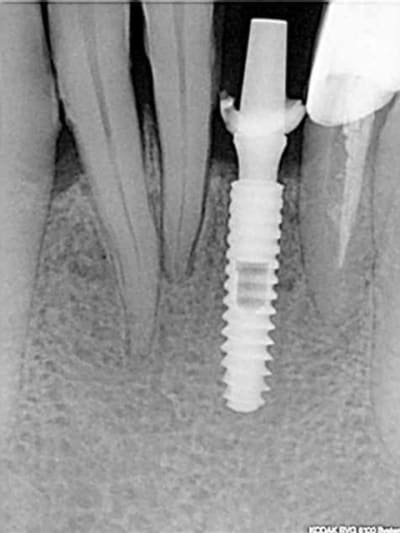

rx à j=0 et j+4 mois

ce qui est surprenant , c'est la présence d'os au niveau du col.

Oui on connait chez Leone mais reproductible sur toute la gamme. C'est qu"est que je dit! Mais nous c'est démontable et indexé. Un vieux cas en rx 5 ans entre les deux rx.